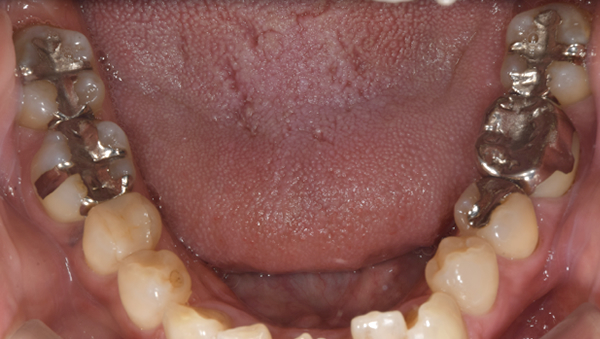

症例1

治療前

治療後

治療内容

口腔内の銀歯を全てセラミックにしたいというご希望でした。親知らずは抜歯しています。笑ったときや自然なスマイルをしたときも銀歯が見えなくなり自然になりました。

治療期間 約2ヶ月

治療費 合計:935,000円 (内訳)

オールセラミック:110,000円×5本

セラミックインレー:55,000円×7本

治療のリスク・副作用 銀歯の下で虫歯が大きくなっていたら歯の中の神経をとらないといけないことがあります。また、被せ物を外すと、ご自身の歯が少ない場合は別途はを残すための処置が必要になることがあります。